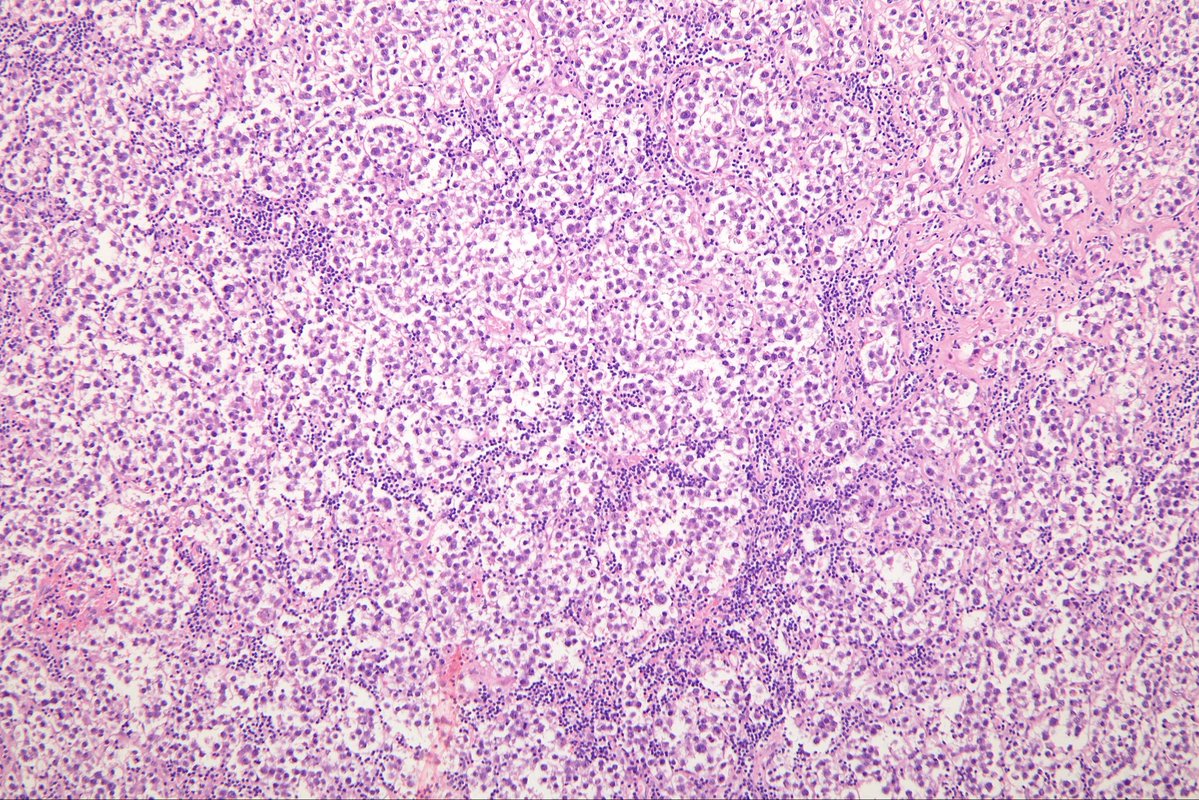

@MirunaPopescu13

DLBCL, NOS showing signet ring cell-like morphology. #hemepath #PathTwitter